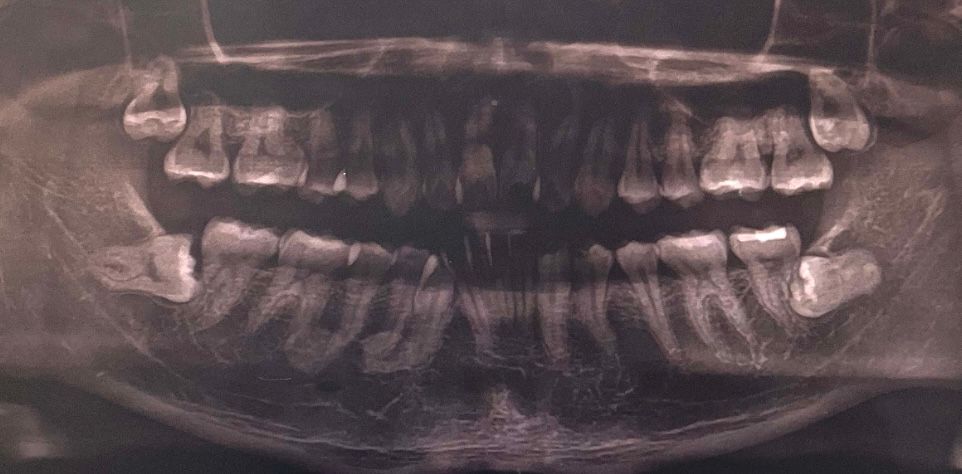

매복사랑니 발치 임플란트 필요한가요?

치과에서 사진 촬영만 하고 의사선생님돠는 상담을 못 했습니다..

사진상 사랑니가 어금니에 영향을 미치는 것 같은데 발치하면 어금니도 같이 발치하고 임플란트를 해야하나요?

사랑니만 발치하고 다르게 관리하는 방법은 없을까요?

현재 매복사랑니가 기울어져 있어 앞의 어금니를 상하게 하고 있기에 빠른시일내에 발치를 하길 권합니다. 어금니는 발치하지 않고 우선 사용을 하고, 만약 어금니도 통증 및 사용이 어려운 경우에는 나중에 발치후 임플란트를 권합니다.

양쪽 아래 사랑니 옆 어금니가 확실히 영향은 받고 있습니다 사랑니 발치중에도 영향을 받을 수 있습니다 이후 증상이 있으면 신경치료 후 크라운을 씌우거나 발치 후 임플란트를 심어야할 수도 있겠습니다

사랑니는 발치를 하고 나서 따로 임플란트를 하지 않으셔도 크게 문제가 되진 않습니다. 사랑니 떄문에 앞치아에 충치가 생겻다면 추가적인 치료가 필요 할수 있습니다